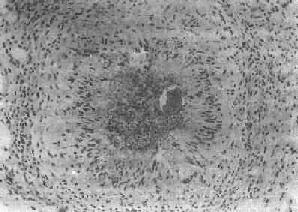

(1)急性虫卵结节:肉眼观为灰黄色、粟粒至绿豆大(0.5~4mm)的小结节。镜下见结节中央常有1~2个成熟虫卵,也偶可多达20个以上。这些成熟虫卵的卵壳上附有放射状嗜酸性的棒状体,也称为Hoeppli现象,用免疫荧光法已证实为抗原抗体复合物。虫卵周围是一片无结构的颗粒状坏死物质及大量嗜酸性粒细胞浸润。因其病变类似脓肿,故也称为嗜酸性脓肿(图19-5)。在坏死组织中可混杂多数菱形或多面形屈光性蛋白质晶体,即Charcot-Leyden结晶,系嗜酸性粒细胞的嗜酸性颗粒互相融合而成。随后虫卵周围产生肉芽组织层,其中有以嗜酸性粒细胞为主的炎症细胞浸润,还有单核巨噬细胞、淋巴细胞、浆细胞及少量中性粒细胞。随着病程的发展,肉芽组织层逐渐向虫卵结节中央生长,并出现围绕结节呈放射状排列的类上皮细胞层。类上皮细胞层逐渐加宽,嗜酸性粒细胞显著减少,构成晚期急性虫卵结节(图19-6),这是向慢性虫卵结节发展的过渡阶段。

血吸虫病之晚期急性虫卵结节

图19-6 血吸虫病之晚期急性虫卵结节

坏死区及嗜酸性粒细胞浸润范围缩小,其周围出现放射状排列的类上皮细胞层